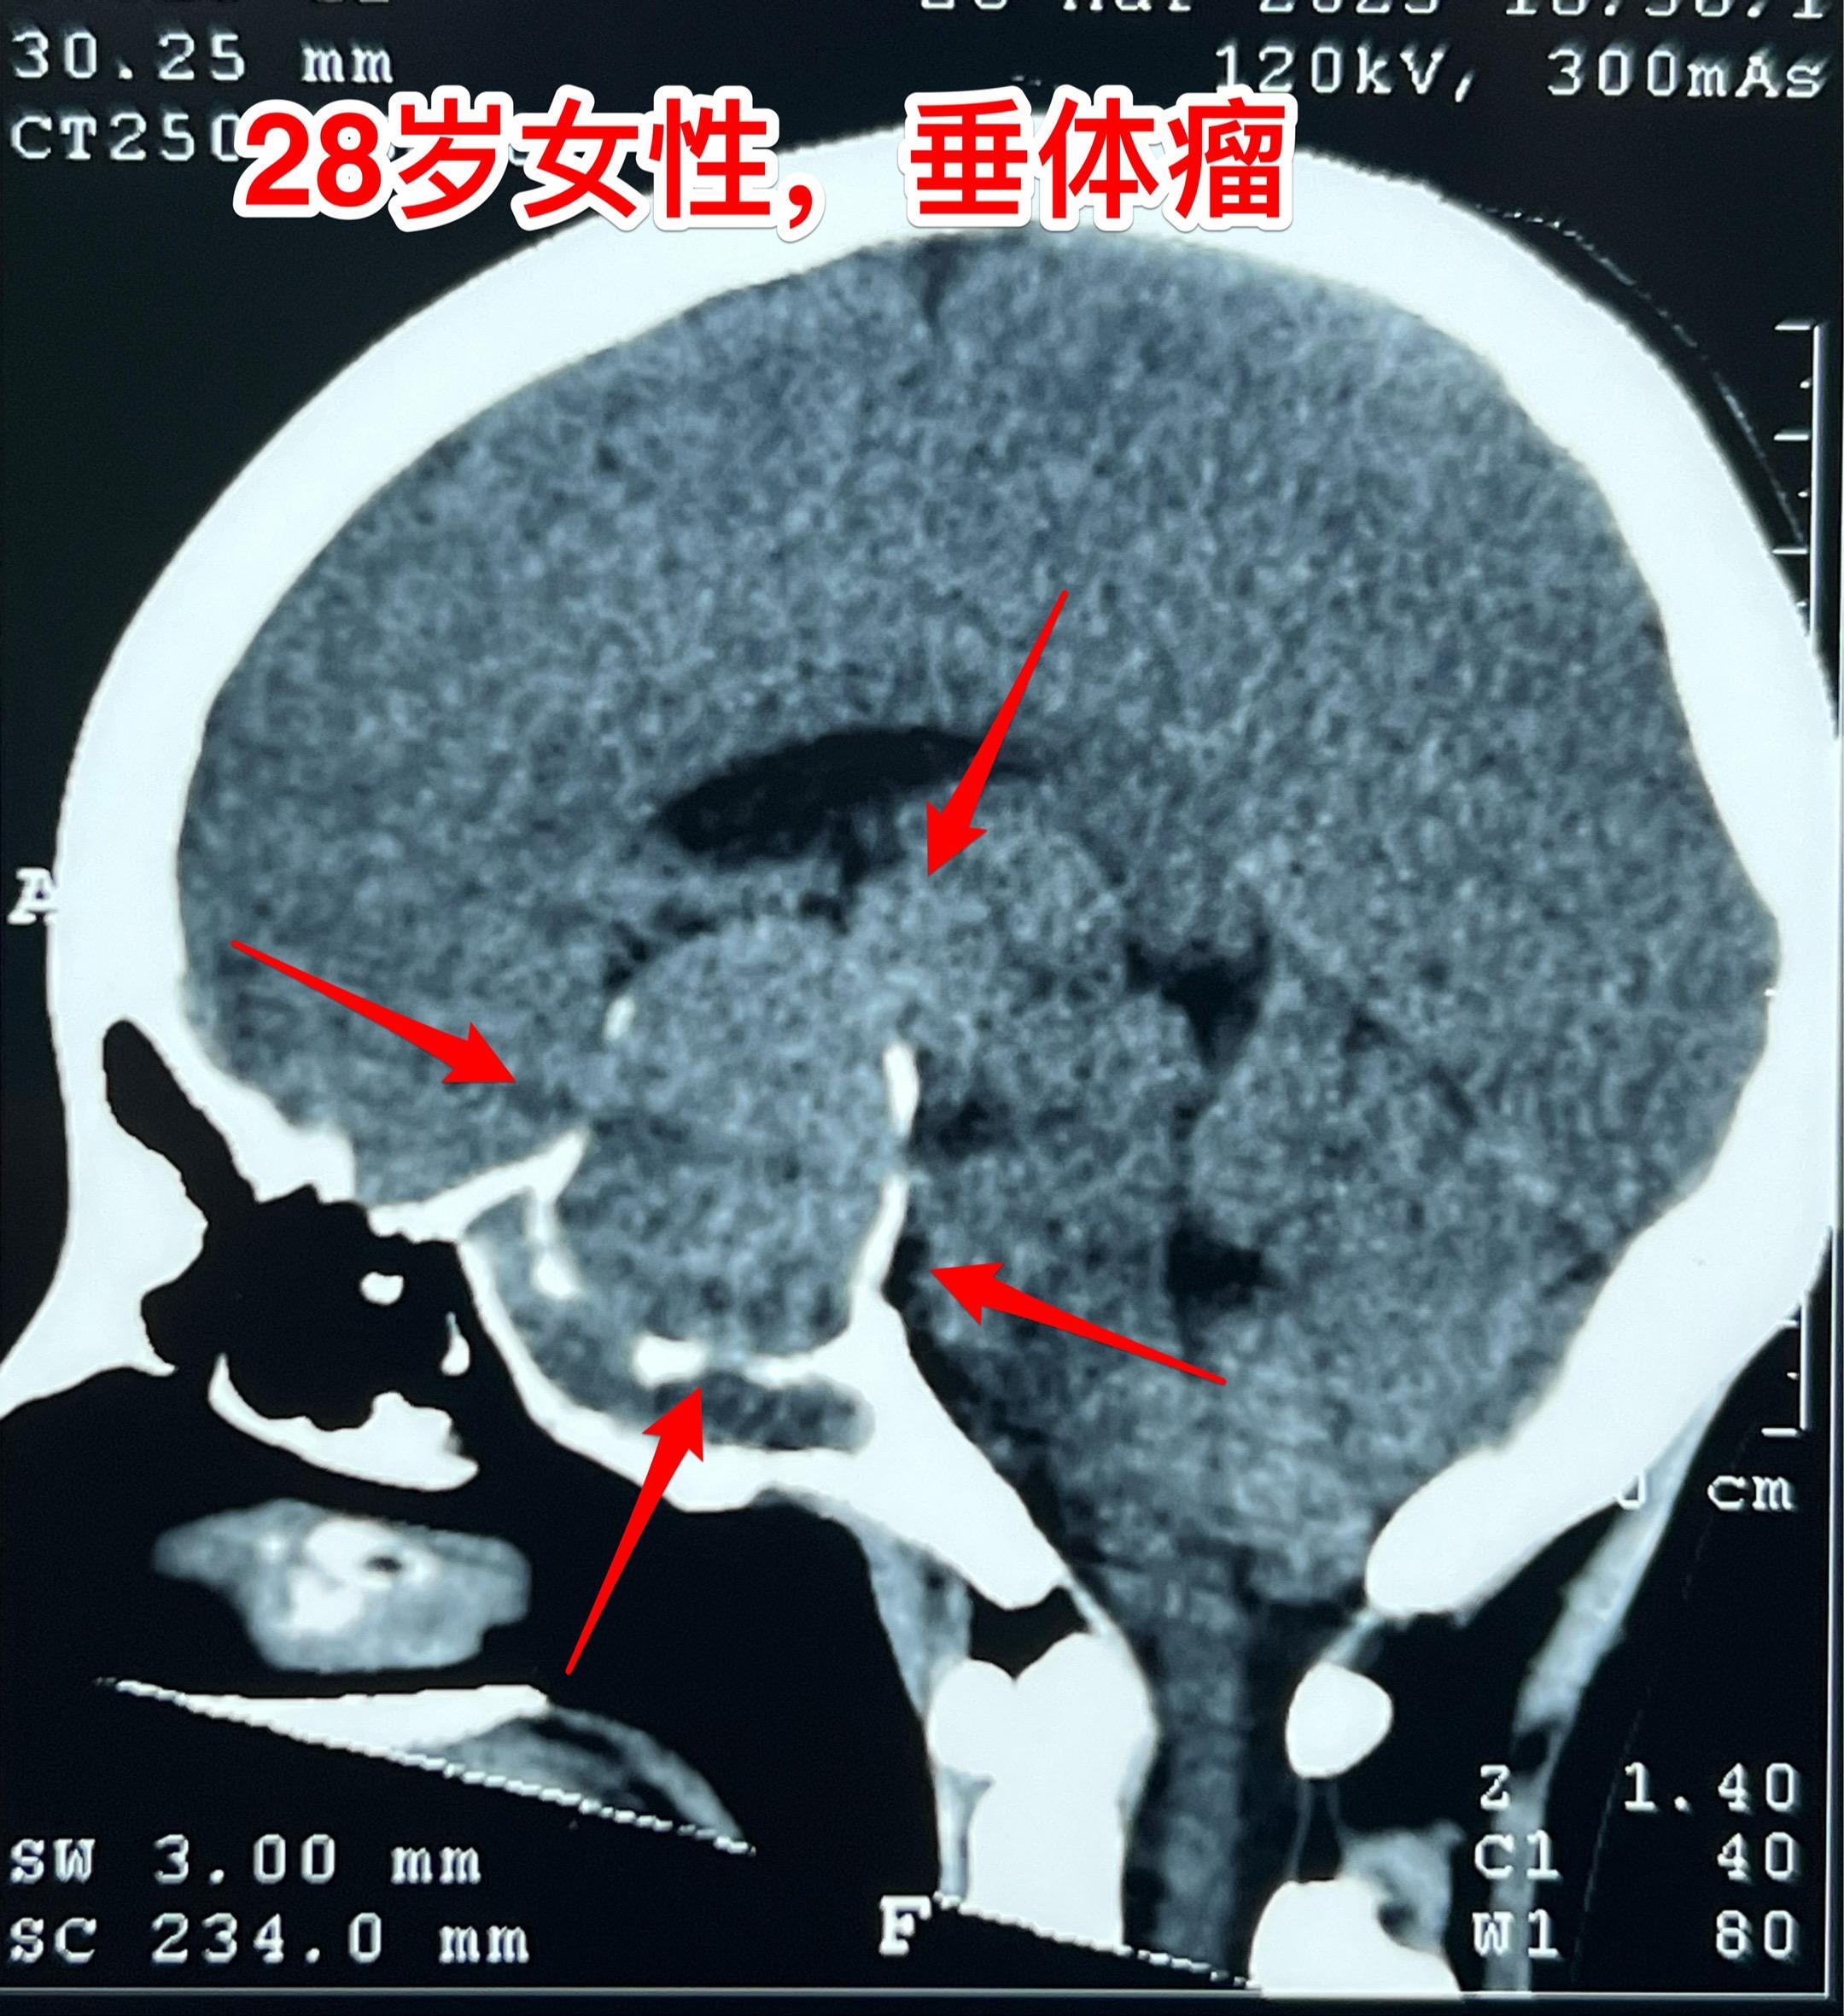

28岁女性6年前生完孩子就一直内分泌紊乱。山西省晋城市28岁女性,6年...

2025-03-31 11:30